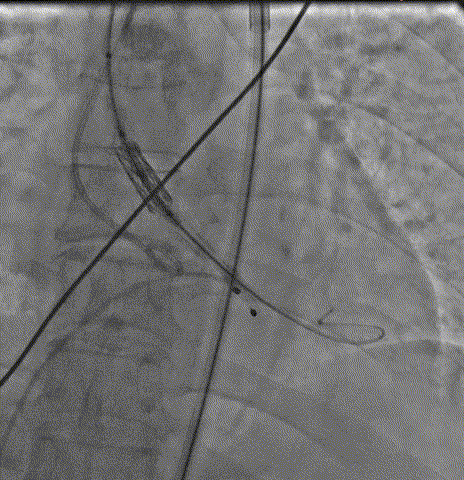

瓣膜输送跨瓣

瓣膜定位后